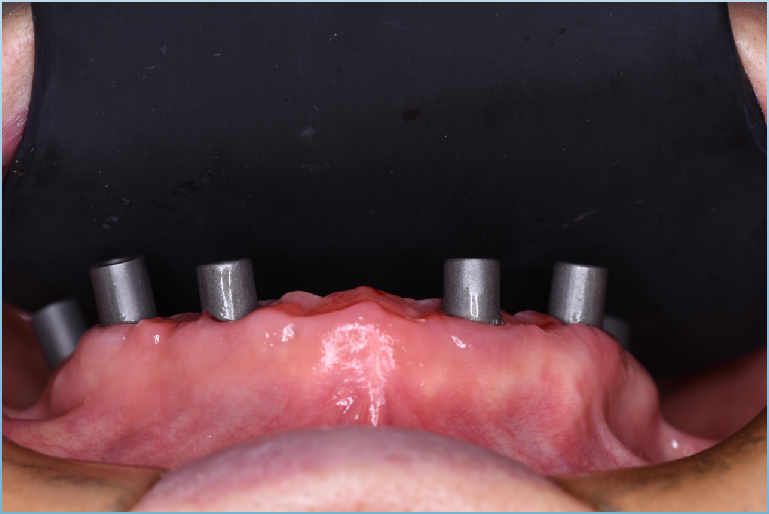

真实案例

TRUE CASE